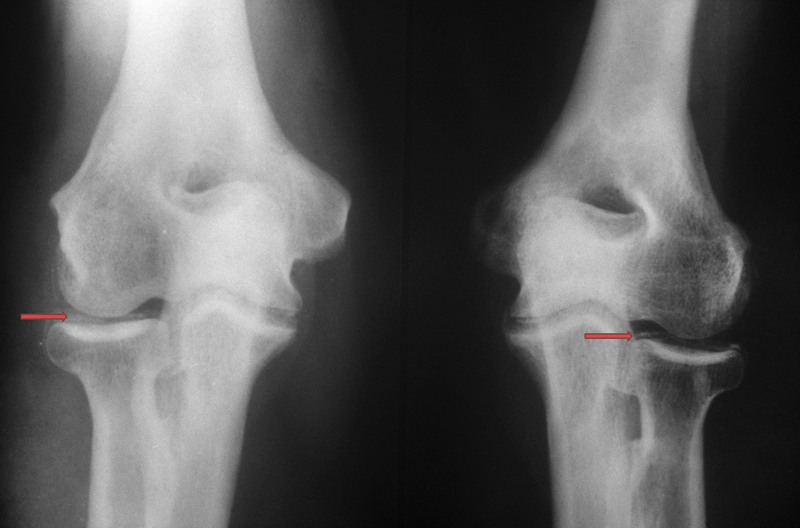

Ảnh chụp X-quang vôi hóa xương khớp

Bác sĩ chuyên khoa sẽ thăm khám lâm sàng, chỉ định các xét nghiệm hình ảnh như chụp X-quang, MRI để đánh giá chính xác mức độ vôi hóa và đưa ra phác đồ điều trị phù hợp, giúp ngăn chặn bệnh tiến triển, giảm đau và cải thiện chất lượng cuộc sống.

Khi phát hiện các dấu hiệu vôi hóa xương khớp, bước đầu tiên là thăm khám chuyên khoa để được chẩn đoán chính xác và tư vấn phác đồ điều trị phù hợp. Bác sĩ sẽ dựa vào kết quả thăm khám lâm sàng, hình ảnh (X-quang, MRI) để xác định mức độ và vị trí vôi hóa.